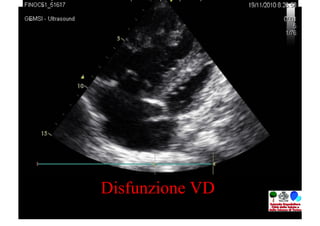

CURARE

•  Trattare l’IP per migliorare i sintomi e la qualità di

vita, MA ANCHE per prevenire la disfunzione

destra

•  L’IP puo’ essere “trattata”

•  La disfunzione destra è IRREVERSIBILE

Disfunzione VD